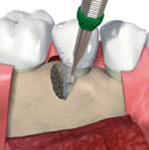

zahušťování kosti a její roztahování pomocí speciálních nástrojů spreading, kondenzace, distrakce

- Postupné nasazování nástrojů se zvětšujícím se průměrem vede k rozšiřování a zahušťování kosti